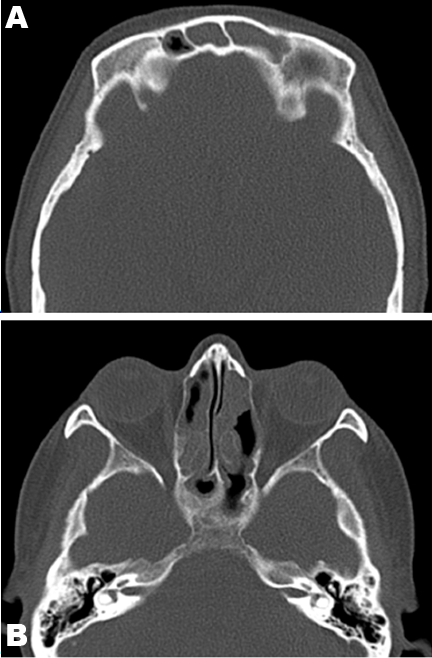

The patient’s routine chest X-ray was normal. Computed tomography (CT) scan of the chest revealed a focal ill-defined alveolar opacity in the peribronchial region of the left lower lobe apical segment and another smaller similar opacity in the left upper lobe centrally (Figure 1). Computed tomography scan of the sinuses (Figure 2) showed near complete opacification of the frontal and the visualized ethmoid sinuses with mild mucosal thickening throughout the maxillary, sphenoid, and ethmoid sinuses and hypertrophy of the turbinates.

The patient was commenced on prednisolone (50 mg/day) and this was associated with a marked improvement in her symptoms. She reported no dyspnea or wheeze, and the neuropathic pain and paresthesia in her left arm decreased substantially. The prednisolone dose was slowly tapered and is still ongoing. Her last computed tomography scan of the chest (performed after three months of treatment with corticosteroids) shows complete resolution of the previously visualized areas of ground glass opacities in the left lower lobe.

Figure 1: Computed tomography of the chest showing focal ill-defined opacities in the left lower lobe.